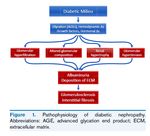

InsulinaLa Nefropatia Diabetica è quasi un «modello sperimentale» per testare l’effetto nefro-

protettivo dei farmaci bloccanti il R.A.S. Questi farmaci sono in grado di

ridurre la Pressione Idrostatica Intra-glomerulare contrastando l’ Iperfiltrazione

Glomerulare ed il passaggio di proteine attraverso la barriera glomerulare (Proteinuria)

SII farmaci bloccanti il RAS possono rallentare la progressione

della Nefropatia Diabetica riducendo la proteinuria e

rallentando la progressione della malattia renale??

Gli Inibitori del co-trasporto Sodio/Glucosio

(SGLT-2, Empagliflozin, Canagliflozin, Dapagliflozin)

agiscono bloccando il co-trasporto Sodio/Glucosio a livello del tubulo prossimale

generando natriuresi e glicosuria

Una maggiore delivery di sodio a livello della macula densa potrebbe “eccitare” il

Feed-back tubulo glomerulare determinando vasocostrizione della Arteriola afferente

riducendo la pressione intra-glomerulare e quindi, ad esempio,

riducendo l’iper-filtrazione la proteinuria e la progressione della Nefropatia Diabetica

(trials ENPA-REG, CANVAS)